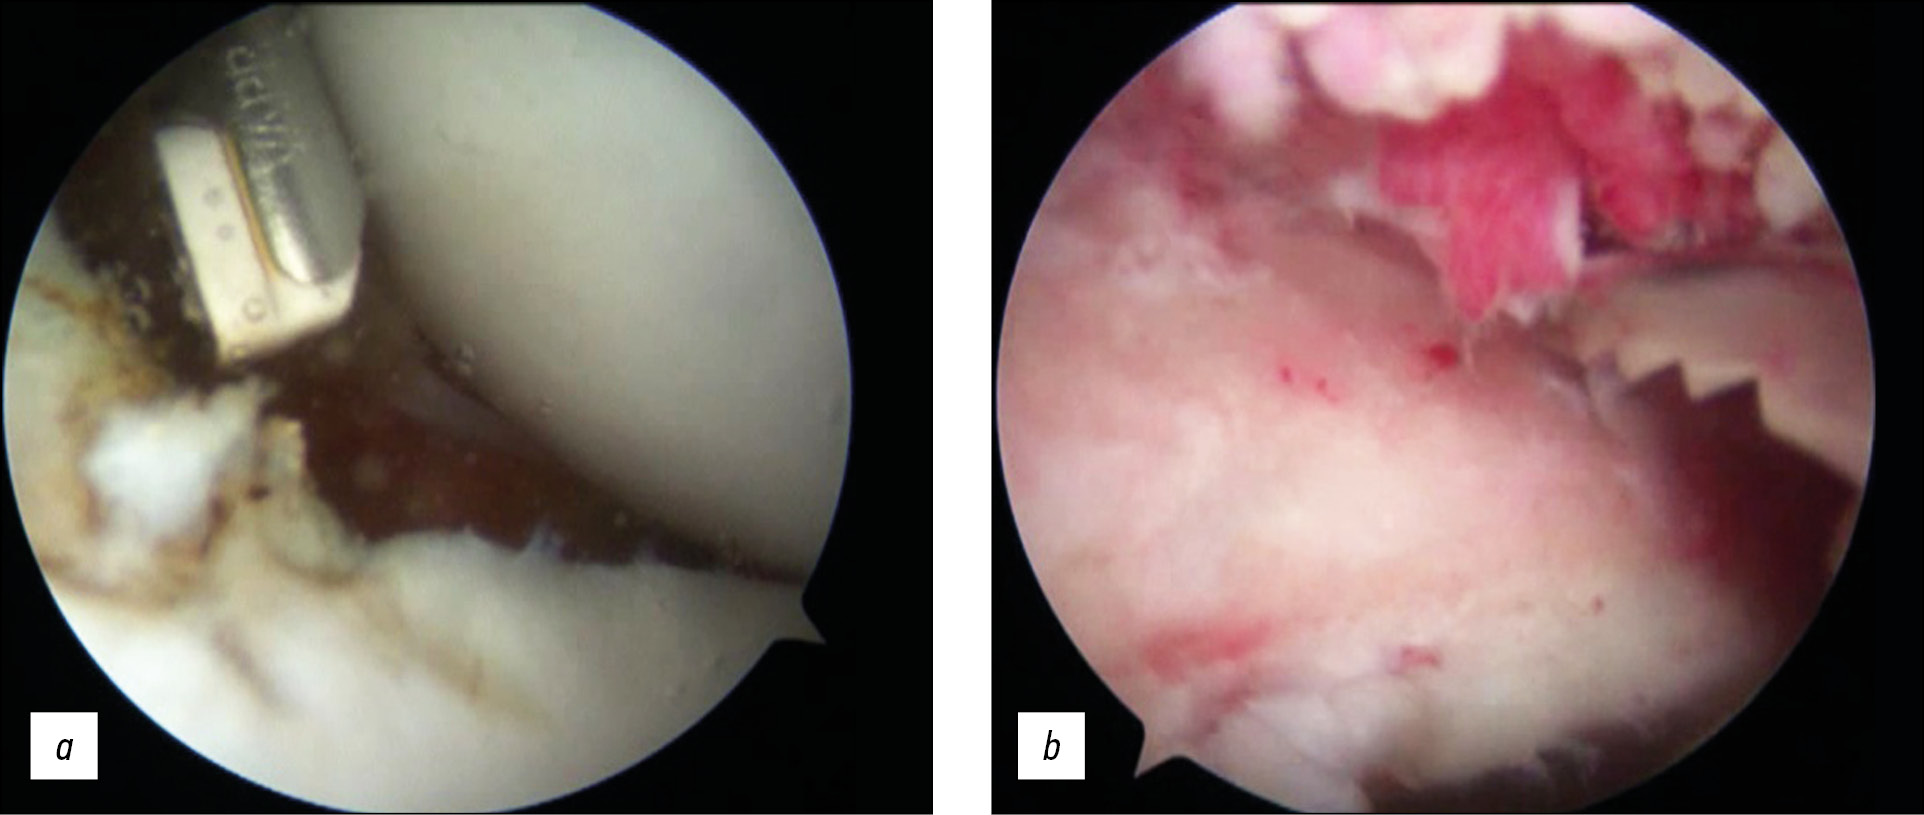

In Stage 2, the arthroscope was transferred to the anterior port, and the main nerves (n. axillaris and n. musculocutaneus) were visualized (Fig. 6). The area of damage to the articular surface of the scapula and the lower edge of the coracoid process were decorticated until pinpoint bleeding appeared (Fig. 7), thereby reducing the risk of bone autograft splitting during its collection, and increasing the contact area, congruence between the cavity of the scapula and the coracoid process (Fig. 8).

Fig. 8. Treatment of the articular surface of the scapula: a — treatment of the anterior-lower section using a coblator; b — use of a rasp in the antero-inferior glenoid region.